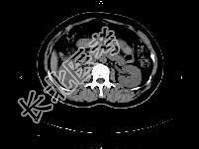

- 单项选择题女,27岁, 寒战高热、尿频、尿痛3天,尿检: 白细胞(+++),CT平扫及增强扫描如图所示, 下列说法错误的是 ( )

A、右肾体积增大

B、增强后右肾实质内可见条片状密度减低区

C、左肾未见异常

D、考虑为急性肾盂肾炎

E、考虑为慢性肾盂肾炎